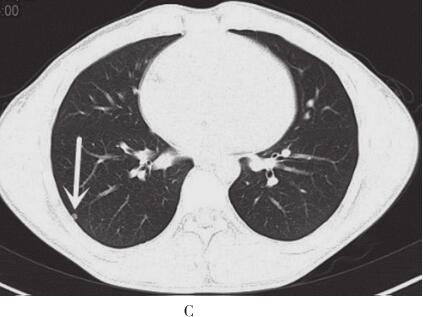

图2 2012年11月15日胸部CT平扫+强化

A.右肺中叶内侧段可见大小约5.7cm×5.0cm软组织肿块,有浅分叶,边缘清晰;B、C.双肺可见多发大小不等结节灶;D.肿块增强扫描呈中度强化